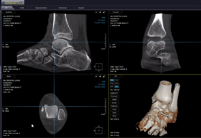

- Weight bearingCT에서 얻어지는 영상 획득 - Polygon 세그멘테이션 정보에서 골성 지표를 추출하여 뼈를 구분 - Bounding box를 통한 족부 족관절 질환 구분 - Key point(Poly line)을 통한 족부질환 예측 및 구분

- 데이터 예시

![]() |

|

| 데이터 수집/정제 | Bone segmentation |

|---|---|

| 질환 bounding box | 4 key-point angle 추정 |